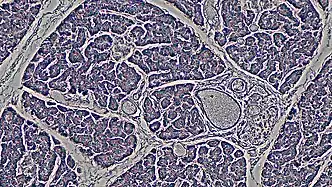

Ductal cells comprise about 10% of the pancreas by number and about 4% in volume. Its function is to secrete bicarbonate and mucins and to form the tubule network that transfers enzymes made by acinar cells to the duodenum. Ductal cells have a proliferation rate of about 0.5% in normal adults, but mitotic activity goes up when the pancreas is damaged.[3]

The ductal pancreas network originates from the central pancreatic duct—this main duct with the bile duct opens into the duodenum. The ductal cells of the main pancreatic duct are bound by connective tissue and produce a columnar epithelium.[3] Interlobular ducts originate from the main pancreatic duct and connect the various pancreatic lobes. In these lobes, the intercalated ducts expel acini. Meanwhile, the ductal cells of these intercalated ducts create a simple squamous epithelium that rapidly converts into simple cuboidal, and connective tissue also surrounds them.[3] As the ducts grow larger, the epithelium becomes cuboidal or columnar (when large in diameter, the ducts become stratified cuboidal), and connective tissue surrounds them. Pancreatic ductal cells are very similar to ductal cells of other exocrine glands (liver, bile duct, salivary glands).[3] Because of this, a common diagnosis affects these cells: cystic fibrosis.

- "cross section: human pancreas". Berkshire Community College Bioscience Image Library. 2019-04-18. Retrieved 2022-12-07.